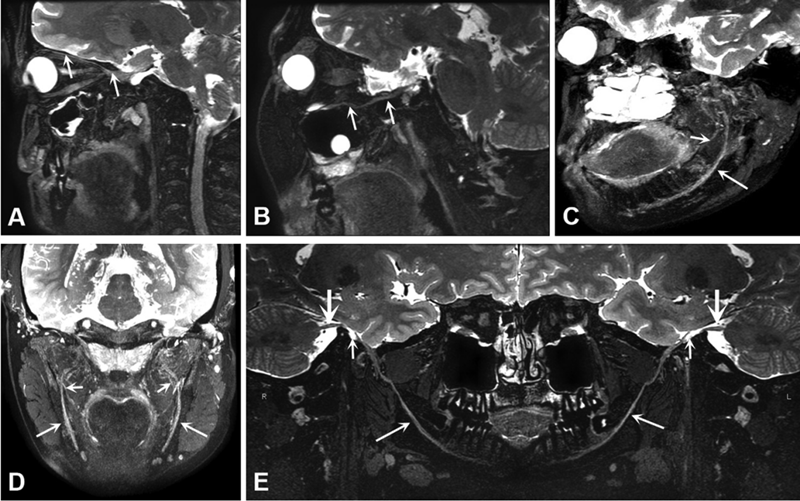

近日,美国口腔颌面外科学院、美国口腔颌面放射学会、美国口腔医学学会和美国口腔颌面病理学会正式公布了其旗舰期刊Oral Surgery, Oral Medicine, Oral Pathology and Oral Radiology 2022年度最佳论文(Best Paper Awards)获奖名单,从该刊2021年7月-2022年6月出版的200余篇论文中,评选出了4篇年度最佳论文我校附属医院放射科疼痛神经影像团队成员张川主治医师(博士在读)发表的学术论文:Magnetic resonance neurography in the management of trigeminal neuralgia: a cohort study of 55 patients(DOI:https://doi.org/10.1016/j.oooo.2021.03.003)荣获该刊年度最佳论文,并被美国口腔颌面放射学会(American Academy of Oral and Maxillofacial Radiology,AAOMR)授予Arthur H. Wuehrmann奖。

我校附属医院放射科疼痛神经影像团队长期致力于疼痛影像诊断与微创介入治疗的临床研究工作。本次获奖文章为团队在三叉神经痛领域的阶段性研究成果,团队创新性提出在三叉神经痛的诊断中应关注三叉神经全程各分支、各段的情况,并通过磁共振实现了三叉神经全程及各分支的显像,为三叉神经痛、颌面部疼痛诊断及口腔颌面外科术前评估等提供了全新的视角,具有重要临床意义。